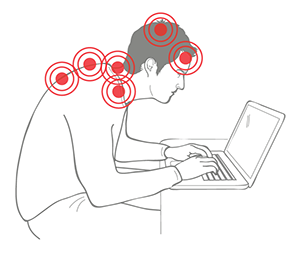

The Backpod and its home program were developed in New Zealand specifically to counter the huge upsurge of pain and headache in people hunching over computers and smartphones.

- Counter the iHunch and actually become taller. Laptops, tablets and smartphones are stunning pieces of technology. But they are also causing upper back pain, neck pain and headache in numbers never seen before. Here’s how you treat and keep your spine flexible and strong - so it’ll handle much bending over these cool devices. The Backpod and its simple home exercise and massage program cover each part of hunching problems - see THE iHUNCH page for more detail. It’s this combination that works - most treatment approaches like gyms or chiropractors cover only one bit, so any improvements don’t last.